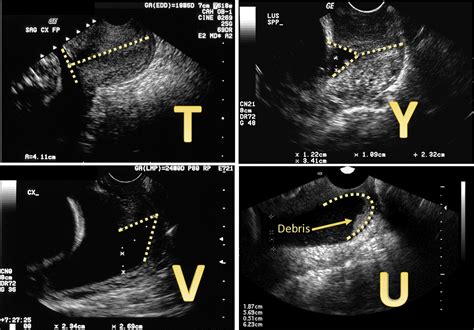

CA Cervix Case presentation | PPTX